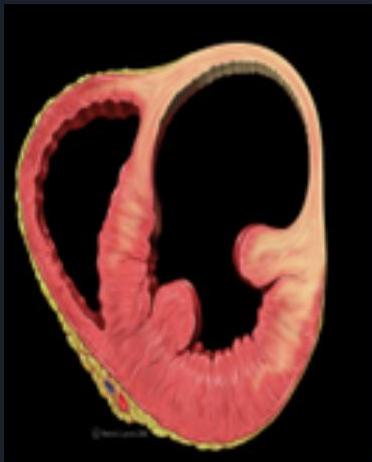

ACS Complications

This Photo β CC BY-SA

Cardiogenic Shock

Heart Failure

Ventricular Tachycardia

Acute MR, VSD

CC BY-SA

Left Ventricular Aneurysm

Persistent ST elevation